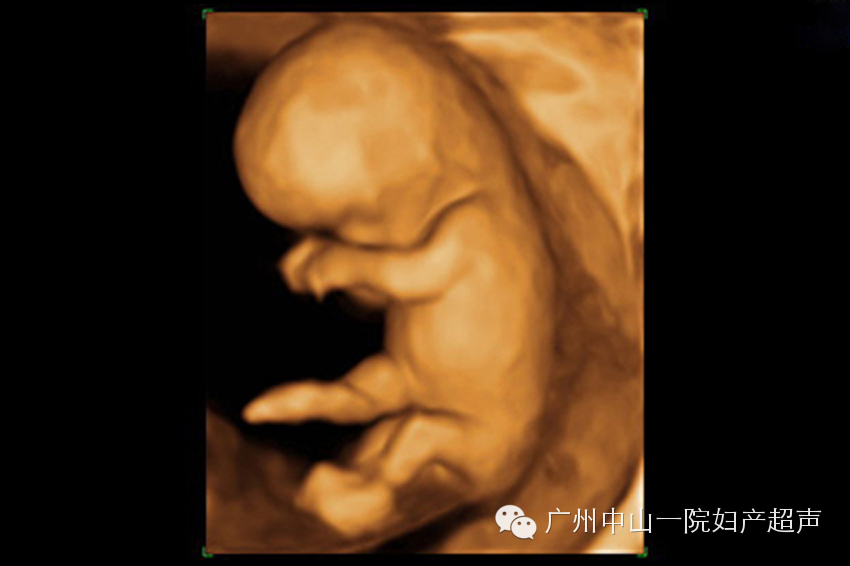

这个时期,宝宝已经初见人形,头部躯干四肢可以分辨出来了,也可以看到宝宝的活动,但是由于宝宝的神经系统高级调控机制仍然没有发育成熟,所以宝宝的活动是像触电一般的全身低级电生理反射活动。但是准妈妈通常在这个时期还无法感知到胎动,只能通过超声观察。运用三维超声可以给宝宝照一张全身照,满足妈妈们的好奇心。

此次检查最重要目的是观察胎儿全身各系统结构是否存在畸形。这个时候,胎儿已经比较大了,三维超声无法获取胎儿的全身照,道理就如同相机无法近距离拍摄大物体的全貌一样。我们通常只建立宝宝的面部三维图像,满足准妈妈们求貌若渴的心情。如果条件良好,宝宝的五官可以清晰的呈现出来,嘴唇、鼻子、眼睛(通常是闭着的)甚至人中都可以一一分辨。对于我来说,工作中最开心的部分就是看着准妈妈们对着宝宝的照片评头论足,感受超声技术的神奇和母子之间的情感交融。